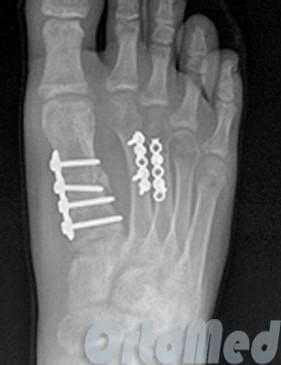

· закрытая репозиция костных обломков предплюсневых и плюсневых костей с внутренней фиксацией (для остеосинтеза используются спицы, винты и пластины различных модификаций);

· открытая репозиция костных обломков предплюсневых и плюсневых костей с внутренней фиксацией (для остеосинтеза используются спицы, винты и пластины различных модификаций);